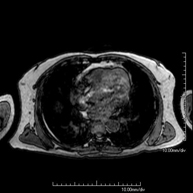

- RM Tórax

Prueba diagnóstica no invasiva que consiste en la obtención de imágenes de alta definición anatómica del tórax mediante el empleo de un campo electromagnético y ondas de radio (con un emisor y un receptor). No utiliza radiación ionizante. Está indicada en aquellas lesiones pulmonares en las que debe descartarse si existe infiltración del mediastino o de la pared torácica, para diferenciar si una lesión torácica es sólida o quística, etc. En ocasiones se deberá emplear contraste paramagnético (Gadolinio) para completar el estudio.